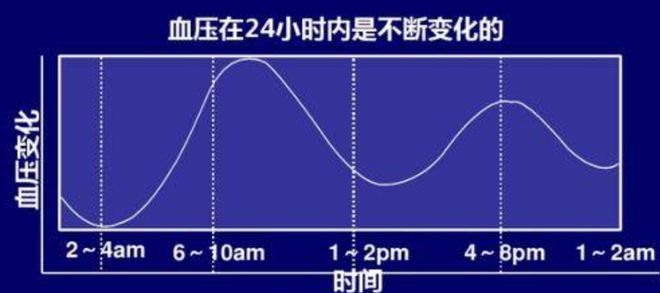

家庭血压监测的建议:家庭血压监测出现血压波动时,应每日早、晚测量血压,每次测量应精准监测,掌握个体规律:

家庭自测 (HBPM): 天热或不适时增加频率(每日早晚)。规范操作: 坐位休息5分钟,测2-3次(间隔1分钟),取平均值。关键时机: 晨起服药前、餐前;晚睡前。详实记录。

动态监测 (ABPM): 波动大或医生建议时采用,是评估金标准。可精准捕捉全天血压(尤其夜间)、识别隐蔽性异常,为医生提供关键依据。

在座位休息5分钟后,测量2一3次,间隔1分钟,记录并取多次测量平均值为当次血压值。通常,早上血压测量应于起床后1小时内、服用降压药前、餐前和剧烈活动前进行。晚间血压测量于晚饭后、睡觉前进行。